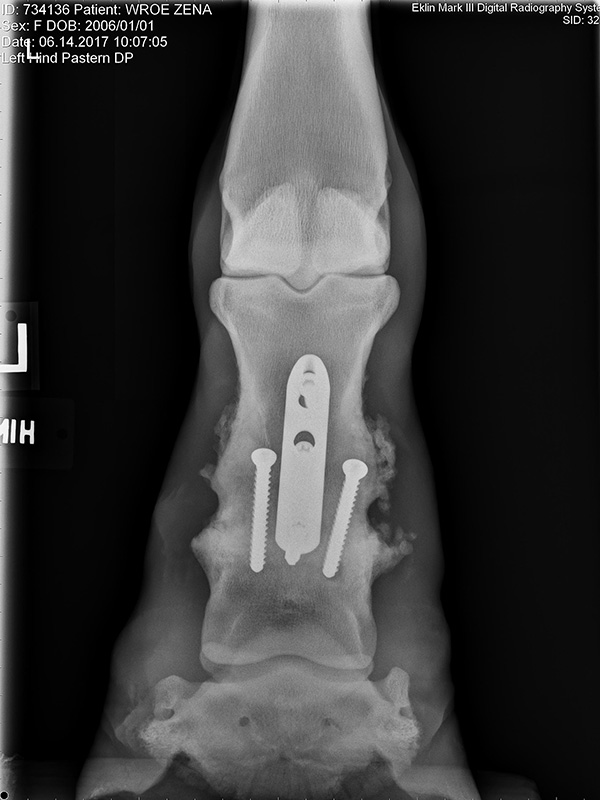

Prior to the study’s publication, Watkins had begun investigating a modified technique for arthrodesis of the pastern joint. That technique accomplished proximal interphalangeal (PIP) joint arthrodesis using a dorsally placed dynamic compression plate (DCP) in conjunction with two abaxially placed 5.5 mm cortex screws applied in lag fashion across the joint. The technique has continued to evolve over the years and today is usually performed using a locking compression plate (LCP) rather than a DCP. In Zena’s case, during her surgery in March of 2017, the pastern joint was exposed, all remaining articular cartilage was removed, the joint was realigned to its normal anatomical position, and a 3-hole LCP interphalangeal plate (PIP plate) was applied in conjunction with transarticular, 5.5 mm cortex screws placed in lag fashion. The PIP plate, a special purpose 3-hole locking compression plate, was designed by the AO Technical Commission’s Veterinary Expert Group (VEEG), specifically for this purpose. Watkins was chairperson of the VEEG at the time the PIP was developed.